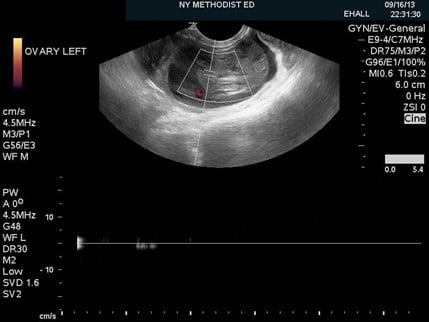

Figure 2. An enlarged, heterogeneous appearing ovary with peripherally displaced follicles and peri-ovarian free fluid

Once the ovary is found, the entire structure should be scanned through in both planes in gray scale. There are several features of torsion that could be apparent in gray scale. When the venous supply becomes cut off, the ovary swells and becomes congested, as seen in Figure 2. This leads to an increase in the size of the ovary, and displaces the follicles peripherally, commonly described as the “string of pearls sign.” Other features that may be apparent are an ovarian mass or large cyst, peri-ovarian or pelvic free fluid, or a twisted vascular pedicle which may result in the “whirlpool sign.”4